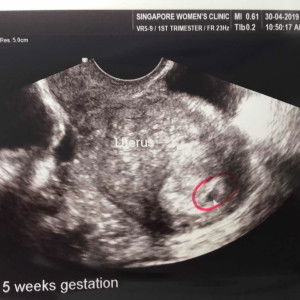

First Trimester

How do you cope with your first trimester? Currently, I just feel so tired, nauseated.. I cant eat anything without feeling like vomiting. But I'm also hungry. What do you guys recommend? Update: Thank you everyone for the lovely reply and support! ❤